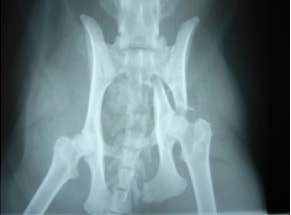

骨盤骨折 : 症例1 | 症例2 | 症例3 | 症例4

症例:交通事故による椎体脱臼

柴犬:9歳、避妊雌

交通事故直後、胸腰部に激しい疼痛、両後肢に完全麻痺を認め、シェフシェリントン徴候を呈していました。レントゲン検査において、第11-12胸椎間の脱臼が認められました。

脊髄の減圧、脊柱管の再構築・安定化を目的に、片側椎弓切除術およびMatrixMANDIBLE Plateによる椎体固定を実施しました。

隣接椎体を架橋するようにプレートを設置しました。

術後レントゲン写真